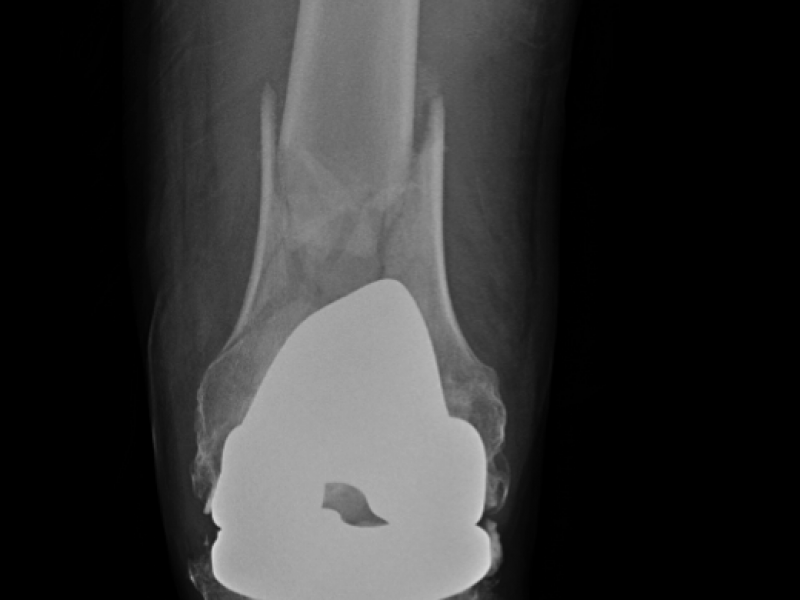

A 63 year-old male with a history of left knee replacement c